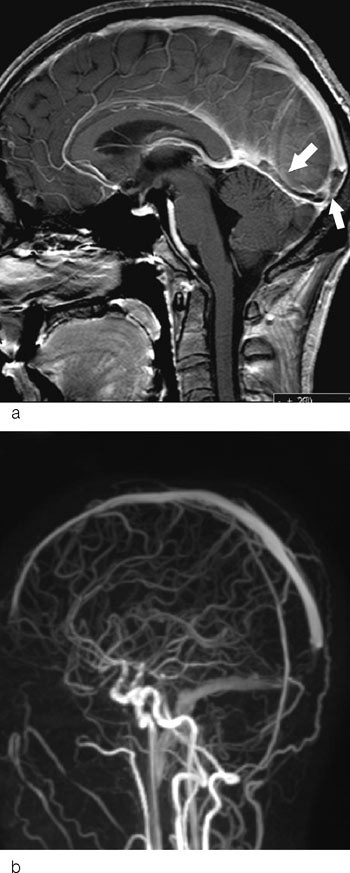

Et typisk bildediagnostisk tegn ved cerebral venetrombose er en fyllingsdefekt i venesinus (fig 1). Disse fyllingsdefektene er hypertette på CT. I sinus sagittalis superior vil fyllingsdefekten ofte ha en trekantet form. På MR vil signalet i tromben variere med alderen (fig 2). Trombene kan også strekke seg retrograd fra venesinus og inn i de kortikale venene. Sekundære forandringer til sinusvenetrombose er hjerneødem og venøse infarkter, typisk beliggende subkortikalt og kortikalt (fig 3). I motsetning til arterielle infarkter vil de venøse ikke følge forsyningsområdene for de store cerebrale arteriene, en annen forskjell er større ødem ved venøse infarkter (18). Venøse infarkter vil ofte være hemoragiske, og på såkalte hemosekvensbilder vil man se blodproduktene som områder med lavt signal.

Ved bildediagnostikk av cerebral venetrombose er det viktig å være oppmerksom på noen fallgruber. Det er en betydelig grad av anatomiske variasjoner i de durale venesinuser, dette gjelder særlig i sinus transversus. Hos vel to tredeler av alle mennesker er høyre sinus transversus større enn venstre. Sinus transversus er hypoplastisk eller manglende på den ene siden hos nær en tredel, vanligvis på venstre side. En manglende fremstilling av sinus transversus må derfor ikke uten videre tolkes som en okklusjon fremkalt av trombe (fig 4). Pacchioni-granulasjoner i venesinuser er en normalvariant (19). Disse granulasjonene kan bli opptil et par centimeter og delvis okkludere venesinus (fig 4). De kan skilles fra tromber ved at de har en typisk lokalisasjon ved innmunningen av Labbes vene i sinus transversus og ved at signalmønsteret er annerledes.